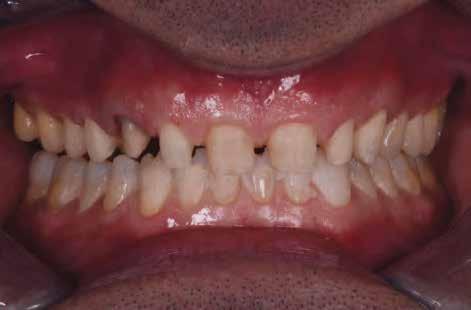

gyorsan és költség - Dr. Miguel Stanley, dr. Ana Gomes Paz, dr. Inês Miguel (Portugália) Dr. Christian Coachman (Brazília) 1. ábra: Kiindulási állapot (frontális irányból). 2. ábra: A kiindulási állapotról okkluzális irányból készített felvétel (felső állcsont). 3. ábra: A kiindulási állapotról okkluzális irányból készített felvétel (alsó állcsont). 4. ábra: A kiindulási állapotról készült panorámaröntgen felvétel (2015).

Esetbemutatás

2015-ben egy 47 éves férfi páciens állkapocs-ízületi panaszai miatt kereste fel a rendelőnket. Ezen felül esztétikai problémát jelentett számára, hogy az egyik felső nagymetszőfogán lévő héj eltört (1-3. ábrák). A klinikai és radiológiai vizsgálatot követően megállapítható volt, hogy a páciens kifejezett bruxizmusa miatt csökkent a harapási magassága, és jelentős mennyiségű saját foganyagot abradált el (4. ábra)